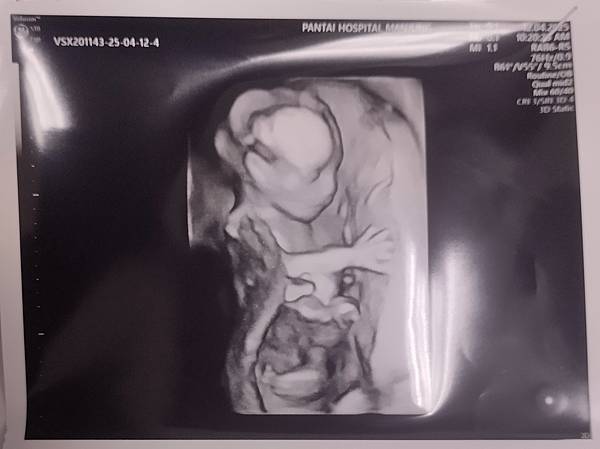

陪著老婆去做產檢

當看著超音波裡顯示出的胎兒

莫名的感到感動

看著她在她媽媽的肚子裡

一天天的長大

也感嘆生命的奇妙